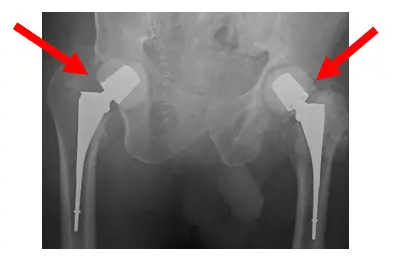

Intraoperative radiographs. Arrows show retractors

Intraoperative control films. Images show cement spacer placement of both femoral heads and necks presumably. X-Rays show high dose antibiotic spacers